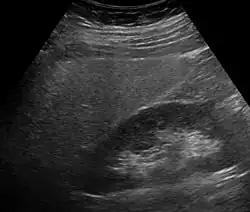

Imaging studies are often obtained during the evaluation process. Ultrasonography reveals a "bright" liver with increased echogenicity. Pocket-sized ultrasound devices might be used as point-of-care screening tools to diagnose liver steatosis.[30] Medical imaging can aid in diagnosis of fatty liver; fatty livers have lower density than spleens on computed tomography (CT), and fat appears bright in T1-weighted magnetic resonance images (MRIs). Magnetic resonance elastography, a variant of magnetic resonance imaging, is investigated as a non-invasive method to diagnose fibrosis progression.[31]